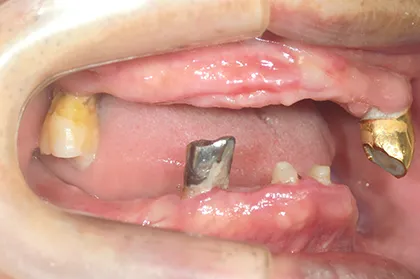

- BEFORE

| 年代・性別 | 70代・男性 |

|---|---|

| 主訴 | 今使っている入れ歯が合わず、嚙むと痛い |

| 治療部位 | 15~26、36、45 |

| 治療内容 | 上下顎インプラント埋入術(上顎5本、下顎2本)を、2回に分けて実施。26部はソケットリフトを適用し、2回法で実施。他部位は1回法。 |

| 金額(税込) | 29,000,000円(税込) |

| 治療期間 | 7カ月(インプラント埋入から上部構造装着まで) 12年経過例(2024年3月時点) |

| リスクと副作用 | 手術部位の腫脹、疼痛 マスダ歯科のインプラント詳細はこちら |